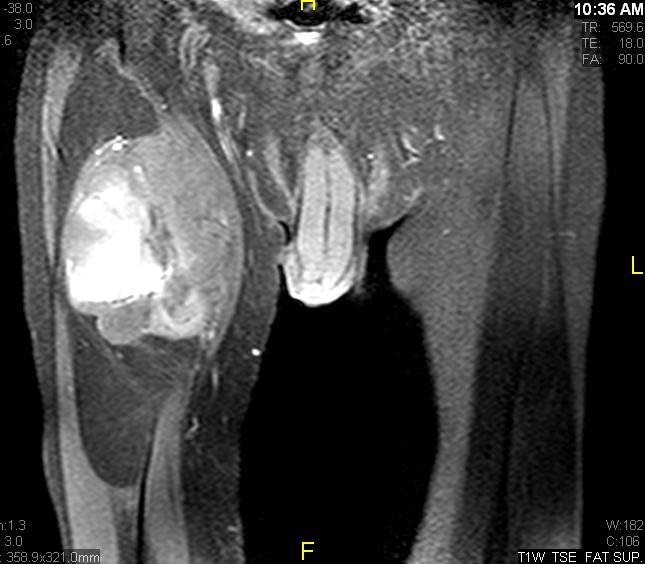

Axial (Fig. 4) and Coronal (Fig. 5) contrasted T1-weighted MR images show a large heterogeneous mass with central and peripheral enhancement. Central low signal intensity image is compatible with necrosis and hemorrhage.

Fig. 11 – 13 Axial (Fig. 11), Coronal (Fig. 12) and Sagital (Fig. 13) contrasted T1-weighted MR images show a large heterogeneous mass with central and peripheral

enhancement. Multiple thick trabeculations. Central low signal intensity image is compatible with necrosis and hemorrhage.

• Contrasted images show hyper-enhancement of the tumors. (Fig. 4, 5, 11-13)